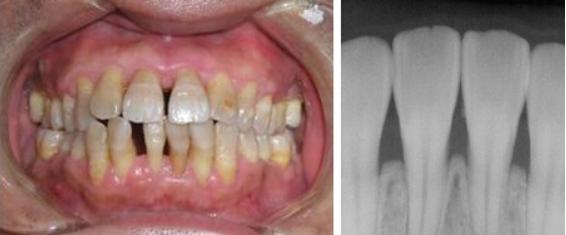

- 牙龈萎缩的初期,我们通过医疗手段给牙龈去除刺激,构建一个健康的牙周状态,牙龈是很可能自行恢复到比较自然健康的状态的。

- 牙龈萎缩的中期,我们可以用药物等手段帮助患者将牙龈萎缩的情况减轻缓解和控制,至少可以叫患者不会因为牙龈萎缩的问题影响用牙。但是这个阶段的牙龈已经无法恢复成它最初的样子了。

通常情况,我们对牙龈问题的治疗都是以重新构建健康的牙周环境为出发点,治疗或者改善牙周疾病为主要方法。争取给患者一个健康的牙周环境,一个健康的牙龈。

如果患者对牙龈的修复问题要求很高,我们也确实有一些尚未特别成熟的牙龈修复处理方式,例如使用有弹性的假牙龈,或者膜龈手术。